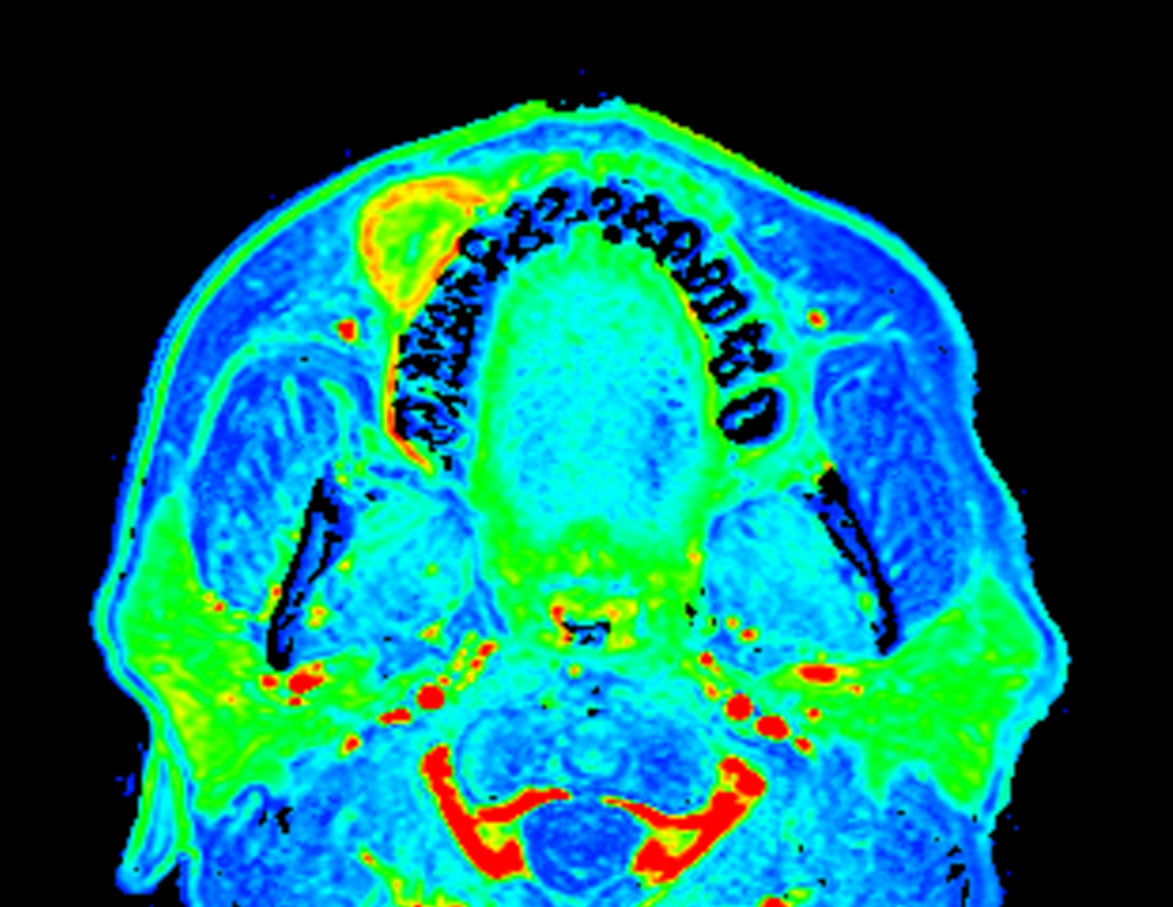

Axial eTHRIVE (area under the curve)

Axial eTHRIVE (max enhancement)

Axial eTHRIVE (wash-in)